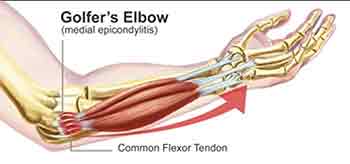

These conditions are usually described as above but are usually due to the attachment of the tendons where they meet the elbow. They will radiate pain all around one side or the other. This common condition does not involve inflammation or swelling of the elbow joint and is amenable to mobilization techniques combined with softening of the attachments. Pain can also extend along the forearm.